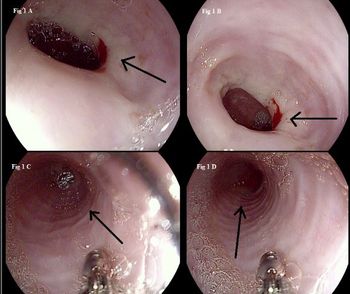

Eosinophilic esophagitis is often misdiagnosed as gastroesophageal reflux disease but does not respond to acid suppression therapy. Here, a close-to-textbook case.

Constipation-related straining may be the cause of the lesion. How would you proceed?